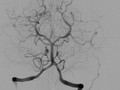

[ISC2015]SWIFT PRIME:支架取栓术治疗卒中更有效

SWIFT PRIME试验表明,在急性缺血性卒中患者中,对大血管前循环闭塞的患者予以溶栓治疗和Solitaire FR(血流恢复)支架取栓术治疗可减少3个月时卒中致残

2015-02-12